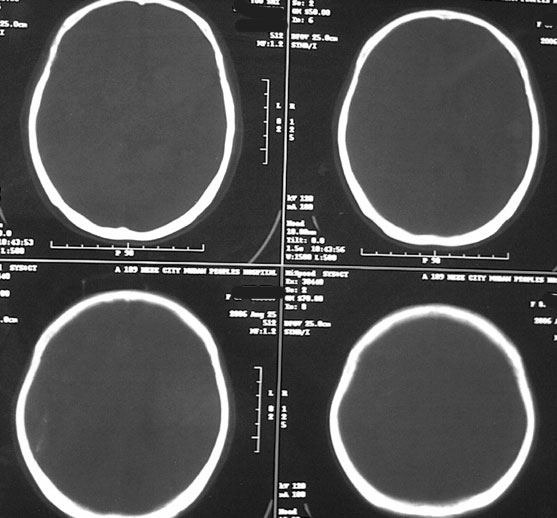

女87左下肢麻木,无外伤史

右颞顶部颅骨内板下新月形混杂密度影,右大脑皮层受压内移,考虑慢性硬膜下血肿,建议增强一下看看病灶,因为平扫好像显示的不是很好;左顶部软化灶

右侧大脑半球脑沟 脑裂变浅或消失,顶叶不规则低密度影,右侧侧脑室明显受压移位,中线偏移,右侧内板下新月形混杂高密度致密影,多考虑:慢性硬膜下血肿.必要时建议强化扫描.

右额颞顶部颅骨内板下方新月形混杂密度影,同侧灰白界限受压内移,右侧脑室呈受压性改变,中线结构左移;左顶叶扫及片状脑脊样低密度区,另可见部分脑沟增宽

ct印象:1.右额颞顶部慢性硬膜下血肿

2.左顶叶软化灶

3.脑部分萎缩